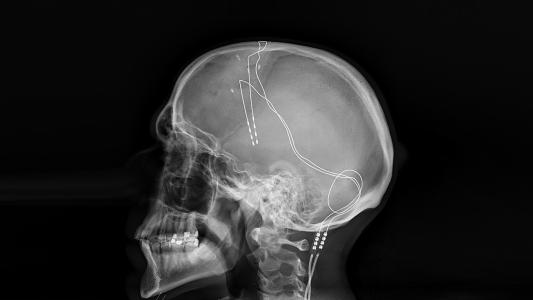

In a new study published in Science, an international team of researchers analyzed impressions left on the skulls of Homo species to better understand the evolution of primate brains. Using computer tomography on fossil skulls, the team generated images of what the brain structures of early Homo species probably looked like, and then compared those structures to the brains of great apes and modern humans.